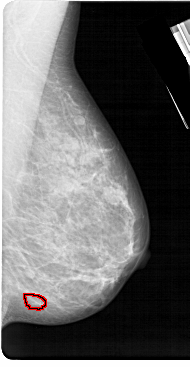

| ics_version 1.0 filename A-1219-1 DATE_OF_STUDY 28 2 1989 PATIENT_AGE 39 FILM FILM_TYPE REGULAR DENSITY 4 DATE_DIGITIZED 8 7 1998 DIGITIZER HOWTEK 43.5 SEQUENCE LEFT_CC LINES 5491 PIXELS_PER_LINE 3016 BITS_PER_PIXEL 12 RESOLUTION 43.5 NON_OVERLAY LEFT_MLO LINES 5491 PIXELS_PER_LINE 3271 BITS_PER_PIXEL 12 RESOLUTION 43.5 NON_OVERLAY RIGHT_CC LINES 5491 PIXELS_PER_LINE 2881 BITS_PER_PIXEL 12 RESOLUTION 43.5 OVERLAY RIGHT_MLO LINES 5491 PIXELS_PER_LINE 2836 BITS_PER_PIXEL 12 RESOLUTION 43.5 OVERLAY |

| FILE: A_1219_1.RIGHT_CC.OVERLAY TOTAL_ABNORMALITIES 1 ABNORMALITY 1 LESION_TYPE CALCIFICATION TYPE PLEOMORPHIC DISTRIBUTION CLUSTERED ASSESSMENT 4 SUBTLETY 2 PATHOLOGY MALIGNANT TOTAL_OUTLINES 1 BOUNDARY |